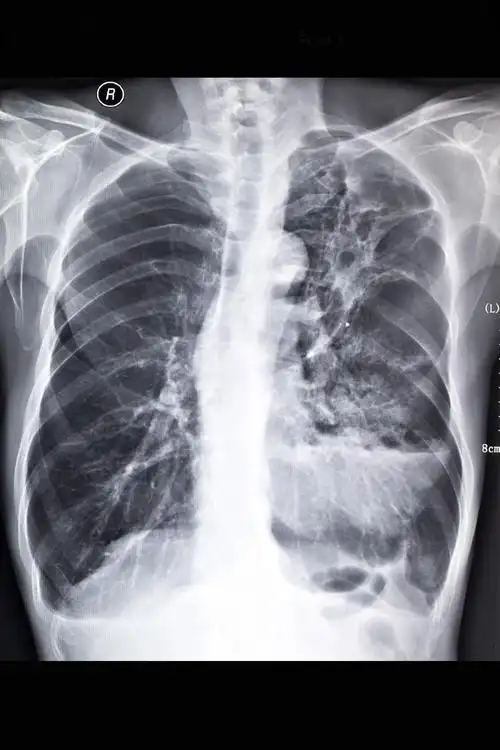

肺纤维化

说"双肺下野肺纹理增强,增粗",请问有可能是"肺纤维化"吗?